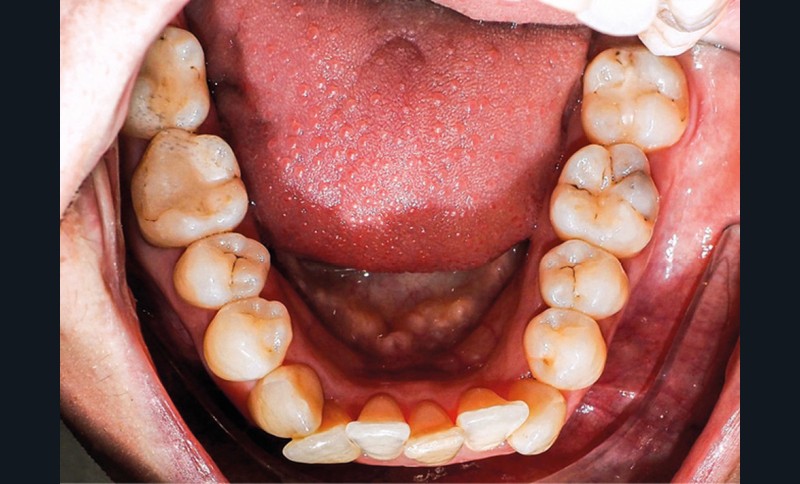

Examen endo-buccal (fig. 2a-e)

L’arcade maxillaire est parabolique, la 12 présente une légère mésio-rotation. L’arcade mandibulaire est également parabolique avec un encombrement antérieur estimé à 6 mm. On note une dyschromie de la 31, dont le test de vitalité est négatif. Le parodonte est fin.

En occlusion, on note une relation de Classe I molaire bilatérale avec un surplomb normal et une supraclusion. Les médianes incisives sont concordantes.

Les incisives maxillaires sont de forme triangulaire [1] et l’indice de Bolton est de 97 % qui traduit la présence d’une DDD par excès mandibulaire.